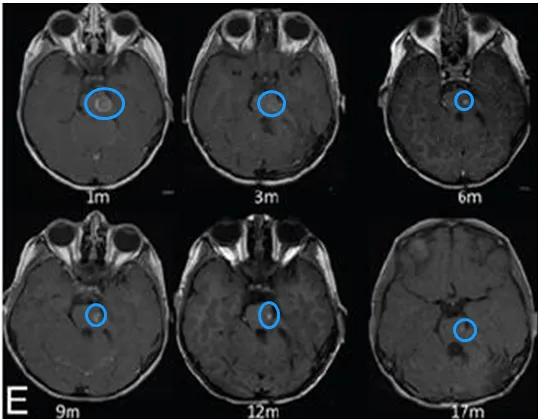

令人欣慰的是,接受激光间质热疗后,患儿未再接受其他化疗,这显著减轻了其身体负担。术后17个月的随访显示,肿瘤未见复发。患儿恢复后已顺利入学,生长与智力发育均处于正常水平,未发现任何功能缺陷,目前仍在接受严格随访。

术后第1、3、6、9、12及17个月随访的轴向T1加权对比增强磁共振成像图像显示,肿瘤体积呈现逐渐缩小趋势。